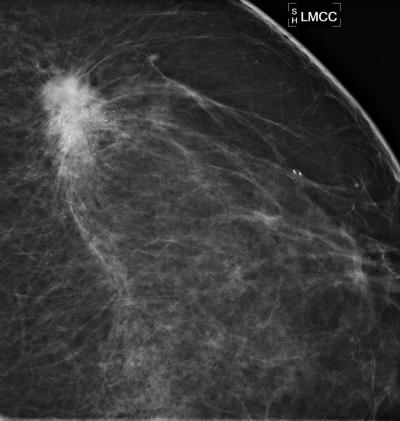

CHICAGO – In a study of screening mammography-detected breast cancers, patients who had more frequent screening mammography had a significantly lower rate of lymph node positivity—or cancer cells in the lymph nodes—as compared to women who went longer intervals between screening mammography exams. Results of the study were presented today at the annual meeting of the Radiological Society of North America (RSNA).

In its earliest stages, breast cancer is confined to the breast and can be treated by surgically removing the cancer cells. As the disease progresses, breast cancer cells may spread to the lymph nodes and then to other areas of the body.

"On its pathway to other places in the body, the first place breast cancer typically drains into before metastasizing is the lymph nodes," said Lilian Wang, M.D., assistant professor of radiology at Northwestern University/Feinberg School of Medicine in Chicago, Ill. "When breast cancer has spread into the lymph nodes, the patient is often treated both locally and systemically, with either hormone therapy, chemotherapy, trastuzumab or some combination of these therapies."

The retrospective study, conducted at Northwestern Memorial Hospital, included 332 women with breast cancer identified by screening mammography between 2007 and 2010. The women were divided into one of three groups, based on the length of time between their screening mammography exams: less than 1.5 years, 1.5 to three years and more than three years. There were 207, 73 and 52 patients in each category, respectively.

Controlling for age, breast density, high-risk status and a family history of breast cancer, the researchers determined that women in the less than 1.5-year interval group had the lowest lymph node positivity rate at 8.7 percent. The rate of lymph node involvement was significantly higher in the 1.5- to three-year and over three-year interval groups at 20.5 percent and 15.4 percent, respectively.

"Our study shows that screening mammography performed at an interval of less than 1.5 years reduces the rate of lymph node positivity, thereby improving patient prognosis," Dr. Wang said. "We should be following the guidelines of the American Cancer Society and other organizations, recommending that women undergo annual screening mammography beginning at age 40."